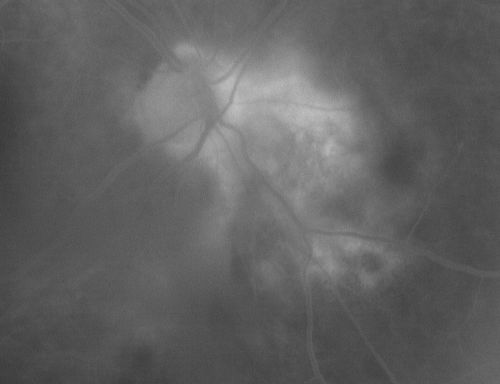

Serpiginouse Choroiditis (Chorioretinitis) - Acute Right Eye - Old Left Eye VA 20/25 OD , 20/50 OS

63-year-old woman has serpiginous choroiditis (date - March 2011).  The right eye has not been previously involved, and then she noticed new onset floaters in the right eye for the last two weeks.  Her vision in the right eye is hazy because of that.

VISUAL ACUITY:  Vision OD is 20/25, OS is 20/50